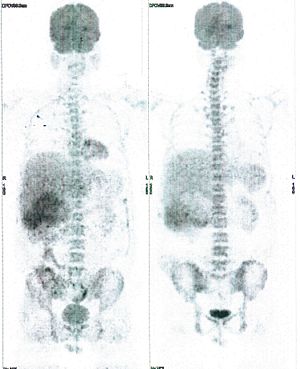

Below are some of the cases, from more than 80 cases we have treated so far with good results. When reading the PET/CT scans, the picture on the left is before treatment, and the picture on the right is after treatment. The intensity of black represents the activity of the cancer, but some black areas are not cancer: brain, heart, radioactive urine in bladder. For the heart, the intensity of black depends on the number of hours of fasting: if more than 10 hours, the heart is not even black, but if fasting is less than 6 hours, it is very black. The intensity of black in the brain can be variable in different scans depending on the brain activity at the time of the scan. The intensity of black in the radioactive urine can also be variable due to the hydration of patients and the time of injection of diuretic.

CASE NO: 4 (PROSTATE CANCER)

A middle-aged man with castration resistant prostate cancer and massive bone metastases, failed all currently available cancer treatment, including with the new and expensive drug XTANDI. After a few treatment, most of the bone metastases went into remission, and the remaining ones are less active. Treatment will continue. Cases no: 3 and 4 show that terminal prostate cancer today can be cured with our new cancer treatment.